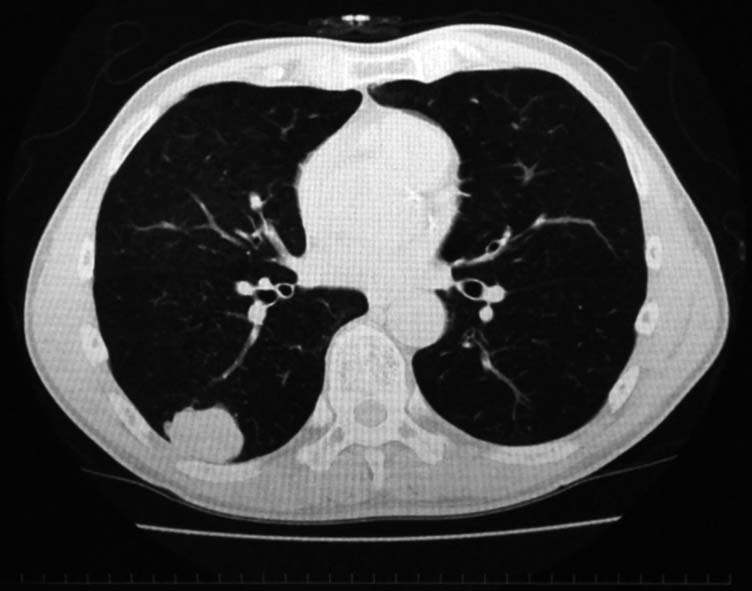

健診で2年ほど肺異常陰影を指摘されていたが自覚症状なく放置. 陰影が次第に増大, 精査のため受診する.

右肺下葉, S6bを主体に一部S9に広がる4.2x3.7x2.5cmの腫瘤. 辺縁凹凸不整, 胸膜に接し内部には不整形の小石灰化がある.肺癌疑い.気管支鏡TBBでは組織片が採取できなかった.

PETで原発巣にSUV max2.2の淡い集積. リンパ節には集積なし. 遠隔転移なし. 肺癌としてはPET集積が淡いが, cT2/1N0M0の肺癌であればstage1B~2Aとなり根治切除可能のためCTガイド下生検が施行された.